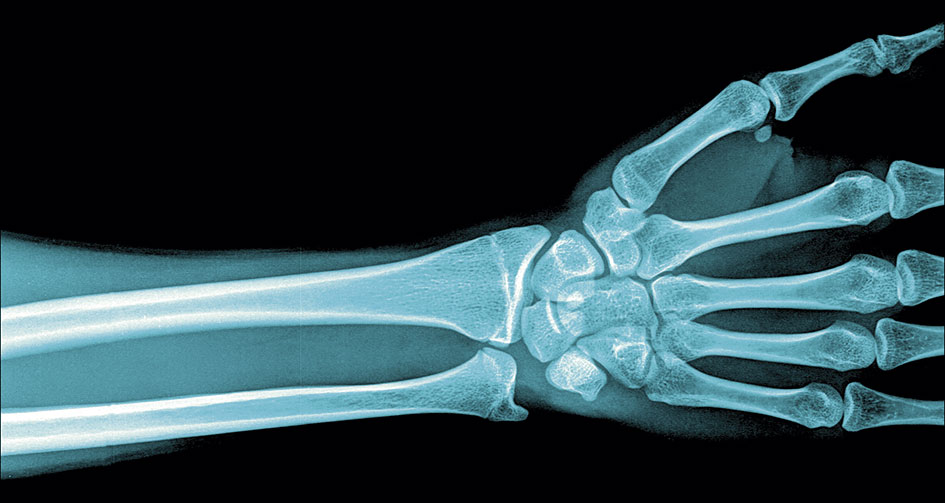

Celiaki och annan malabsorptionssjukdom är associerad med låg bentäthet och ökad frakturrisk, särskilt i radius [8]. Patienter med celiaki har 30 procent ökad risk för fraktur [9]. D-vitaminbrist kan föreligga, och patienter med nydiagnostiserad celiaki kan behöva tillskott av D-vitamin när den glutenfria behandlingen inleds. Sänkt bentäthet och en drygt två gånger förhöjd risk för fraktur har rapporterats efter obesitaskir­urgi [10]. Även i denna grupp kan D-vitaminbrist och annan malabsorption vara bidragande orsaker.